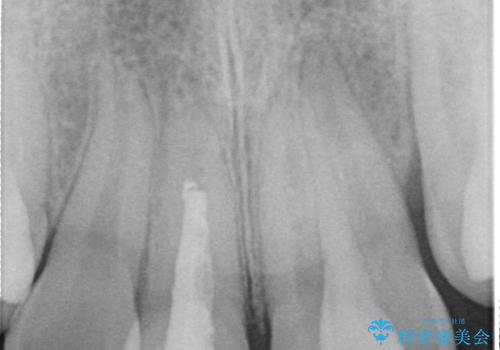

上の前歯は、小さいころにぶつけて折ったとのことで、神経が死んでおり、根の治療が必要な状態でした。

左上の前歯は神経が死んでおり治療が必要な状態でした。また、右上の前歯も根の先に感染がありましたので治療を行いました。